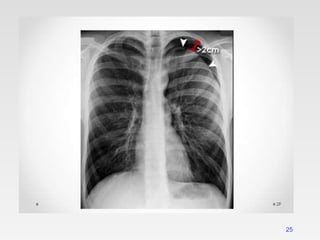

LARGE PNEUMOTHORAX

24

25